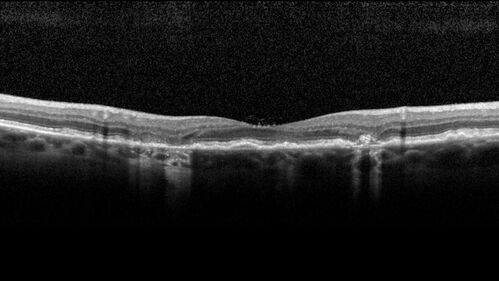

Wet AMD - Occult CNVM and Geographic atrophy

77 year old female with mild vision loss - 20/32 - responded to Avastin